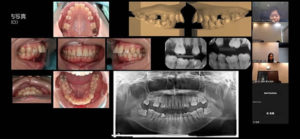

第4回 総合診断実習

リボン歯科グループ内で毎月行われている総合診断実習のWebセミナーです。

当グループ歯科では口腔内や顔貌を含めた精密な検査を行い、多くの歯科医師による診断と治療方針の検討会を行っております。

今回はどうして歯を失ってしまうようになったかということに関する原因を分析して意見を出し合い、診断・治療方針を行うような内容となっていました。

原因が咬合にあって、それをしっかりと把握できないまま治療をすすめてしまうとまた補綴物の脱離や破損を招いたり、次々と他の部位の歯がダメになってしまうことが自分も臨床を行っている中で経験があります。